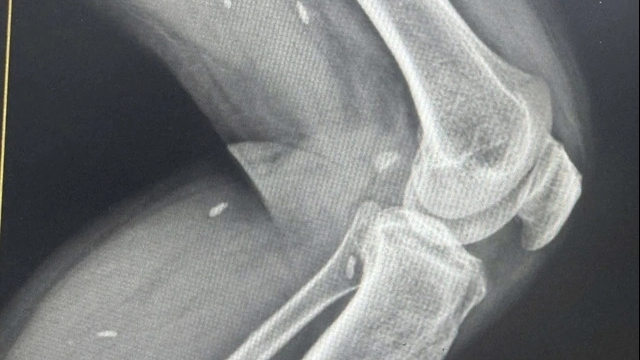

Đau răng là biểu hiện hay bị bỏ qua của nhồi máu cơ tim. Ảnh minh họa: Medicinenet